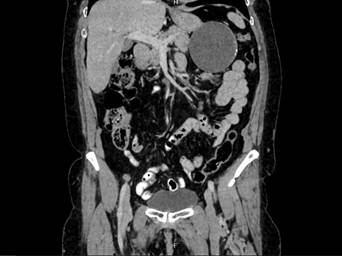

Se realizó una ecografía de abdomen total que informó una imagen quística de 8 x 7 cm, en íntimo contacto con la cola del páncreas. Posteriormente una tomografía computarizada de abdomen con contraste reportó una lesión hipodensa de aspecto quístico, de 86,6 x 78,5 mm, en contacto con la curvatura mayor del estómago, el cuerpo y la cola del páncreas, con paredes irregularmente engrosadas y calcificaciones periféricas aisladas en su interior. Como primera posibilidad se sugirió un tumor del estroma gastrointestinal (GIST, por sus siglas en inglés) (figuras 1 y 2). La endoscopia de vías digestivas altas diagnosticó una gastropatía antrocorporal no erosiva sin hallazgos patológicos adicionales.

Figura 2. Corte coronal de la tomografía computarizada de abdomen donde se señala la lesión hipodensa de aspecto quístico.